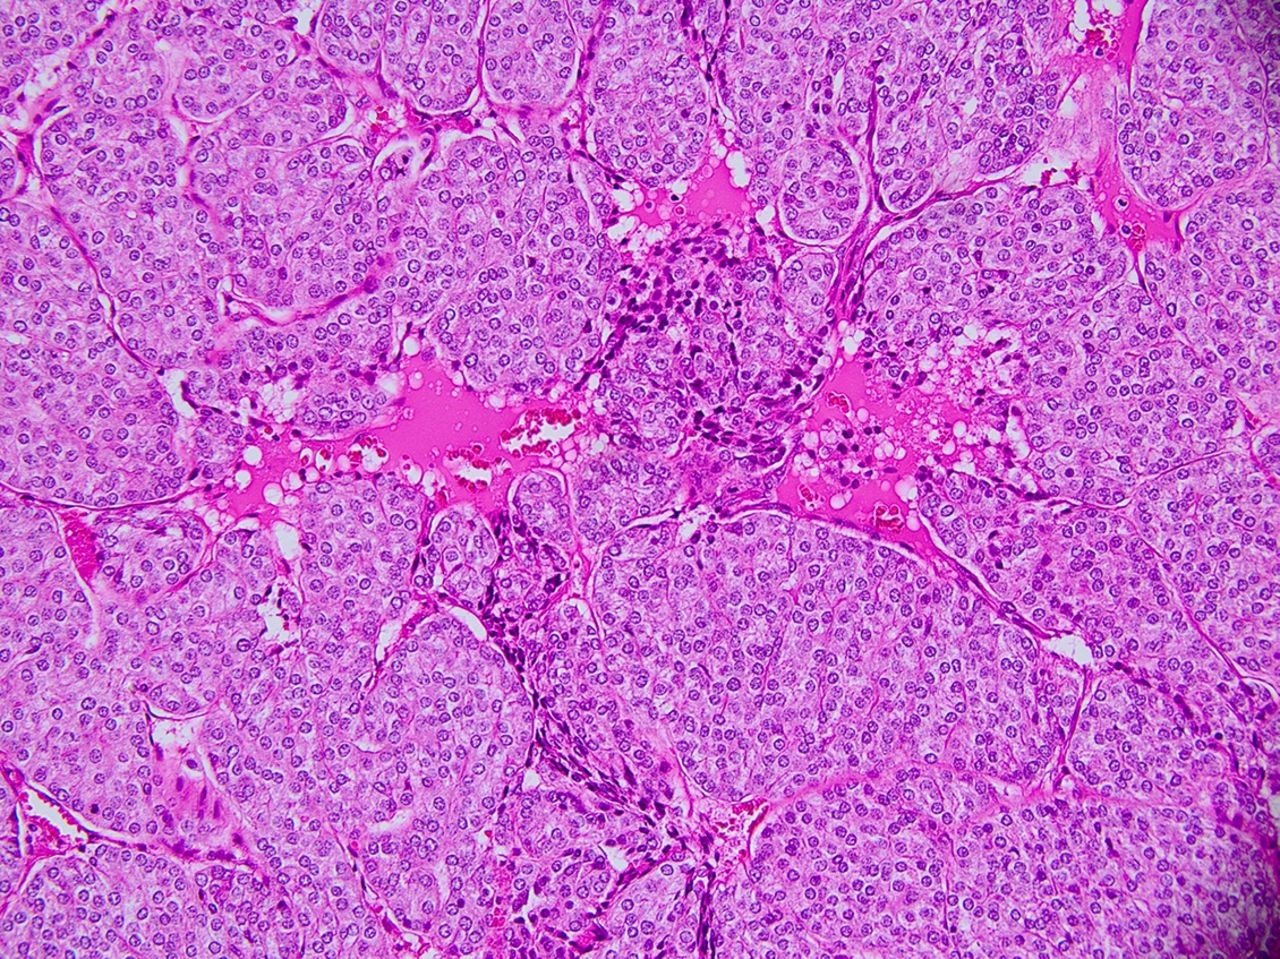

Vậy ung thư tuyến giáp típ nang là gì: Là một dạng ung thư khác biệt do sự tương đồng mô học với mô giáp lành tính và do chức năng khác biệt được bảo tổn.

Ung thư tuyến giáp thể nang bao gồm cả biến thể của nó là tế bào Hurthle thường gặp ở bệnh nhân lớn tuổi và các vùng thiếu i ốt. Thể này thường ác tính hơn ung thư giáp thể nhú, thường theo mạch máu và di căn xa đến xương và phổi.

Việc chẩn đoán ung thư tuyến giáp típ nang không thể phát hiện thông qua xét nghiệm chọc hút tế bào kim nhỏ (FNA) thông thường mà chỉ được phát hiện khi phẫu thuật bóc khối u xét nghiệm mô bệnh học.